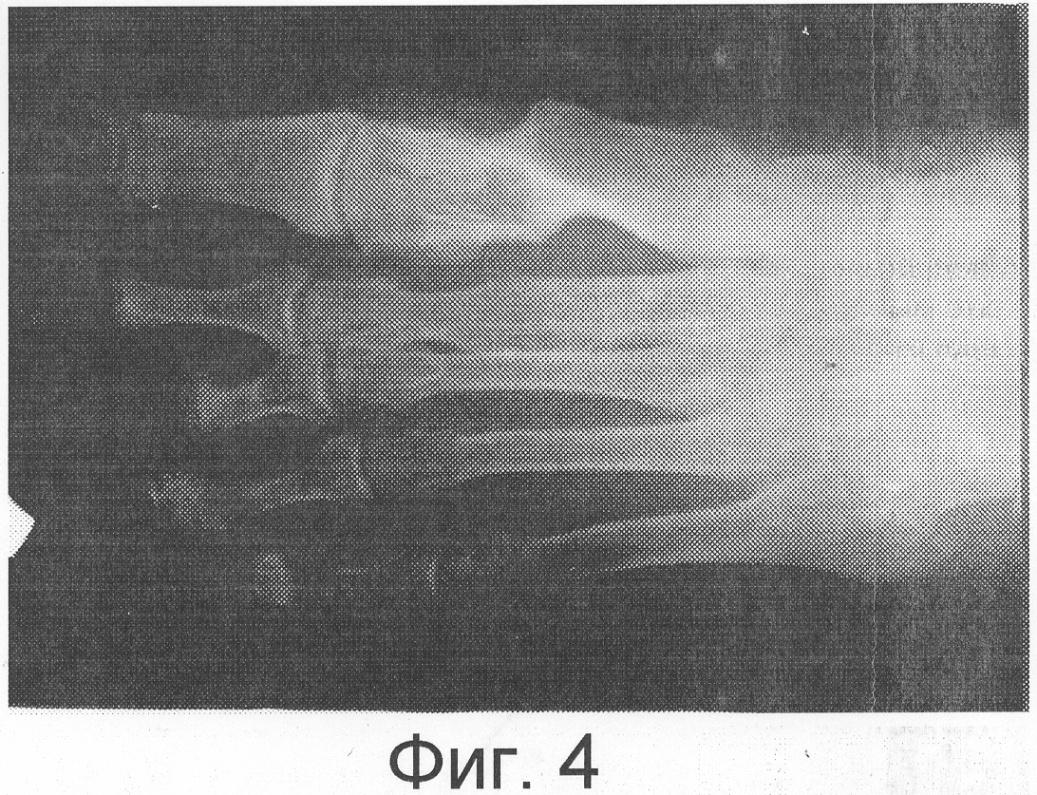

Операционное поле обработано обычным методом. Подкожно по медиальной поверхности 1-го пальца правой стопы до уровня суставной щели 1-го плюснефалангового сустава введена спица Киршнера. Из разреза 3 см в проекции дистальной трети 1-й плюсневой кости с помощью осцилляторной пилы выполнена остеотомия, латерализация 1-го пальца правой стопы, фиксация пальца и проксимального фрагмента 1-й плюсневой кости установленной спицей – клинически деформация устранена. Туалет раны. Рана ушита узловыми швами через все слои. Введены по 2 консольных спицевых фиксатора в проксимальный и дистальный фрагменты 1-й плюсневой кости, которые закреплены во внешних многодырчатых планках, соединенных между собой резьбовыми стяжками. На Фиг.2 представлена рентгенограмма правой стопы в прямой проекции в процессе лечения. На Фиг.3 представлена рентгенограмма правой стопы в боковой проекции в процессе лечения.